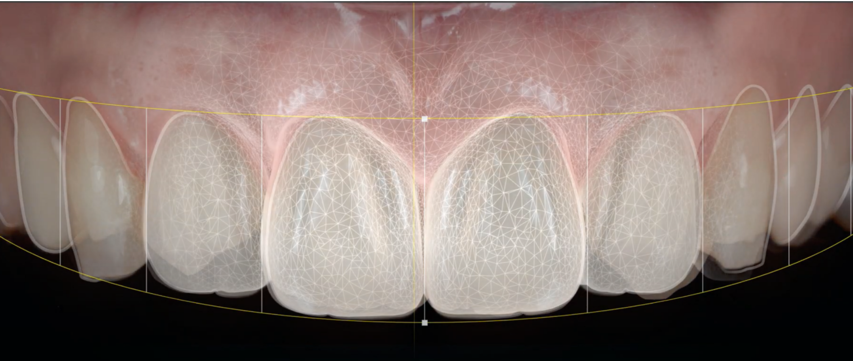

Qu’est ce que la dentisterie restauratrice esthétique ?

La dentisterie esthétique se concentre sur l’amélioration de l’apparence des dents, du sourire et de la mâchoire. Elle diffère de la dentisterie traditionnelle, qui se focalise principalement sur la santé et la fonction dentaire. Les soins esthétiques vous permettent de retrouver un sourire plus harmonieux tout en garantissant le bien-être de vos dents.

Chaque traitement esthétique est adapté à vos besoins spécifiques. L’objectif est d’améliorer l’apparence globale de votre sourire de façon naturelle et durable. Au Cabinet dentaire Claude Monet à Croissy-sur-Seine, une équipe qualifiée vous guide à travers les différentes options de dentisterie esthétique pour obtenir les résultats souhaités.